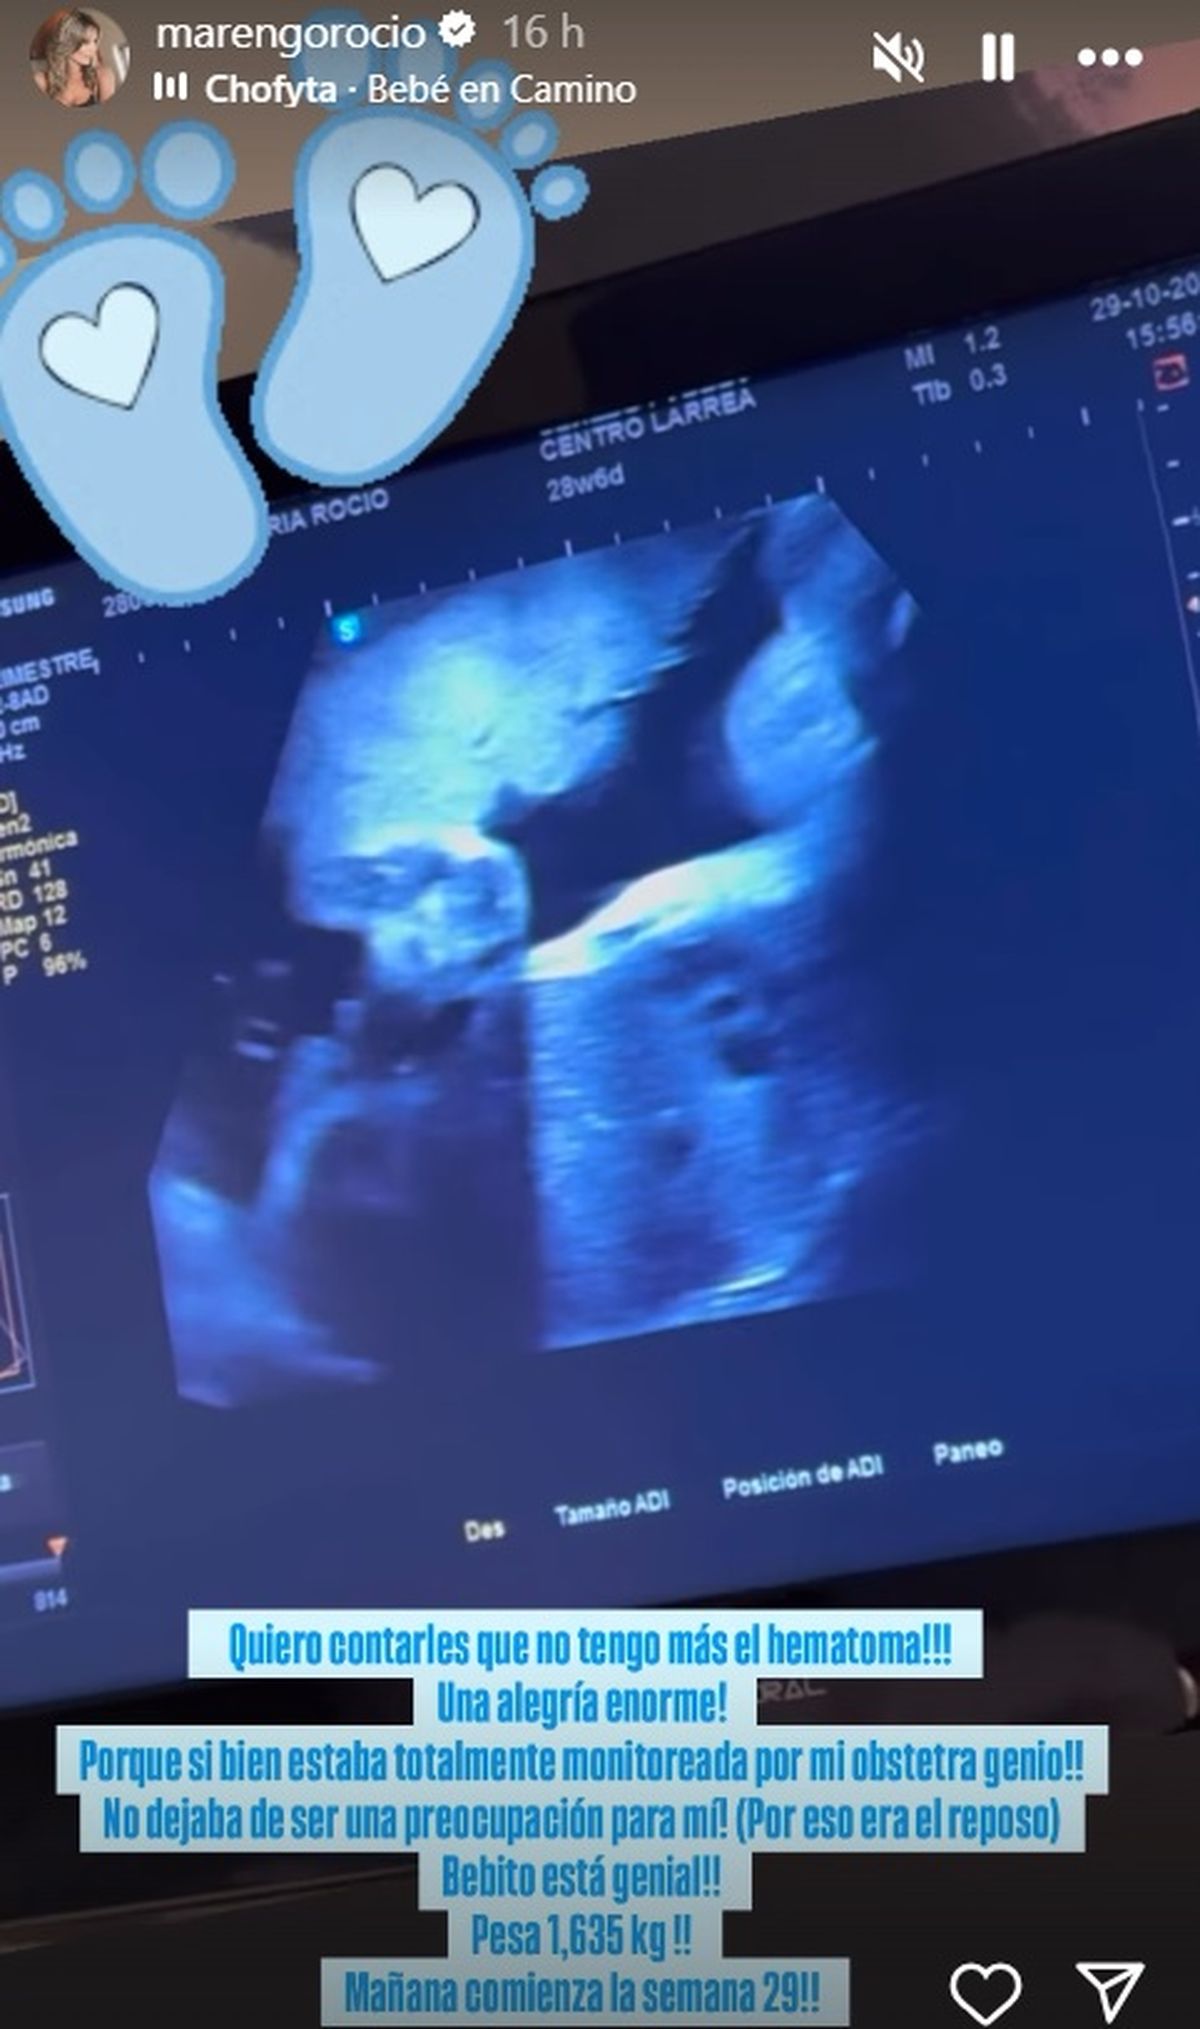

“Quiero contarles que no tengo más el hematoma. Una alegría enorme! Porque si bien estaba totalmente monitoreada por mi obstetra genio, no dejaba de ser una preocupación para mí. Por eso era el reposo. Bebito está genial, pesa 1,635. Mañana comienza la semana 29”, indicó Rocío Marengo desde su cuenta en Instagram.

Después la modelo grabó un video desde sus historias dando más detalles de la buena novedad que tenía para contar: “Como habrán leído la historia anterior, bebito está solito en la panza. No tiene el maldito hematoma que me hizo estar re nerviosa todos estos días. Fueron casi dos meses porque se iba, se achicaba, reposo. Un día libre, volví al reposo", comenzó.

Y detalló sobre ese inconveniente que surgió: “Bebito está a full. El hematoma ese de mier.. que lo vi salir, un asco. El hematoma se iba a moviendo y se puede ir agrandando, por eso hay que hacer reposo para que no crezca. Tenía tres días de reposo y ecografía. Ya me tenía harta".

"Es una porqueria lo que cuento pero es la realidad: el sábado lo expulso. Y el miércoles en la eco ya no estaba más", afirmó Rocío Marengo sobre ese inconveniente que la tenía intranquila.